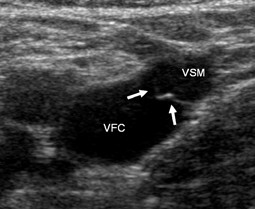

Abb. 4